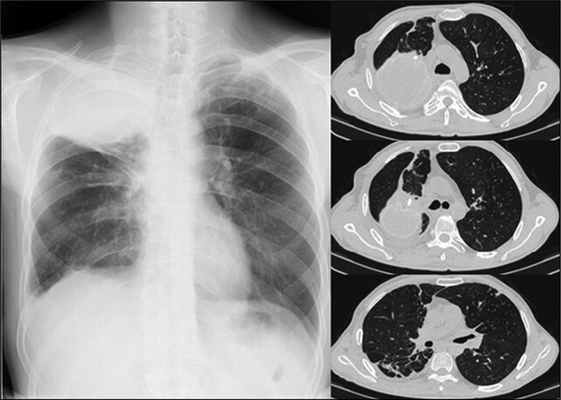

На обзорных рентгенограммах и компьютерной томографии легких определяется фиброзное сморщивание верхней доли и S6 правого легкого, S1–2 левого легкого. Множественные разнокалиберные тонко- и толстостенные каверны: крупные в верхних отделах и мелкие в нижних отделах правого легкого (рис. 1).

Рис. 1. Рентгенографическое (А) и КТ (Б) исследование органов грудной клетки у больного А. при поступлении (описание в тексте)